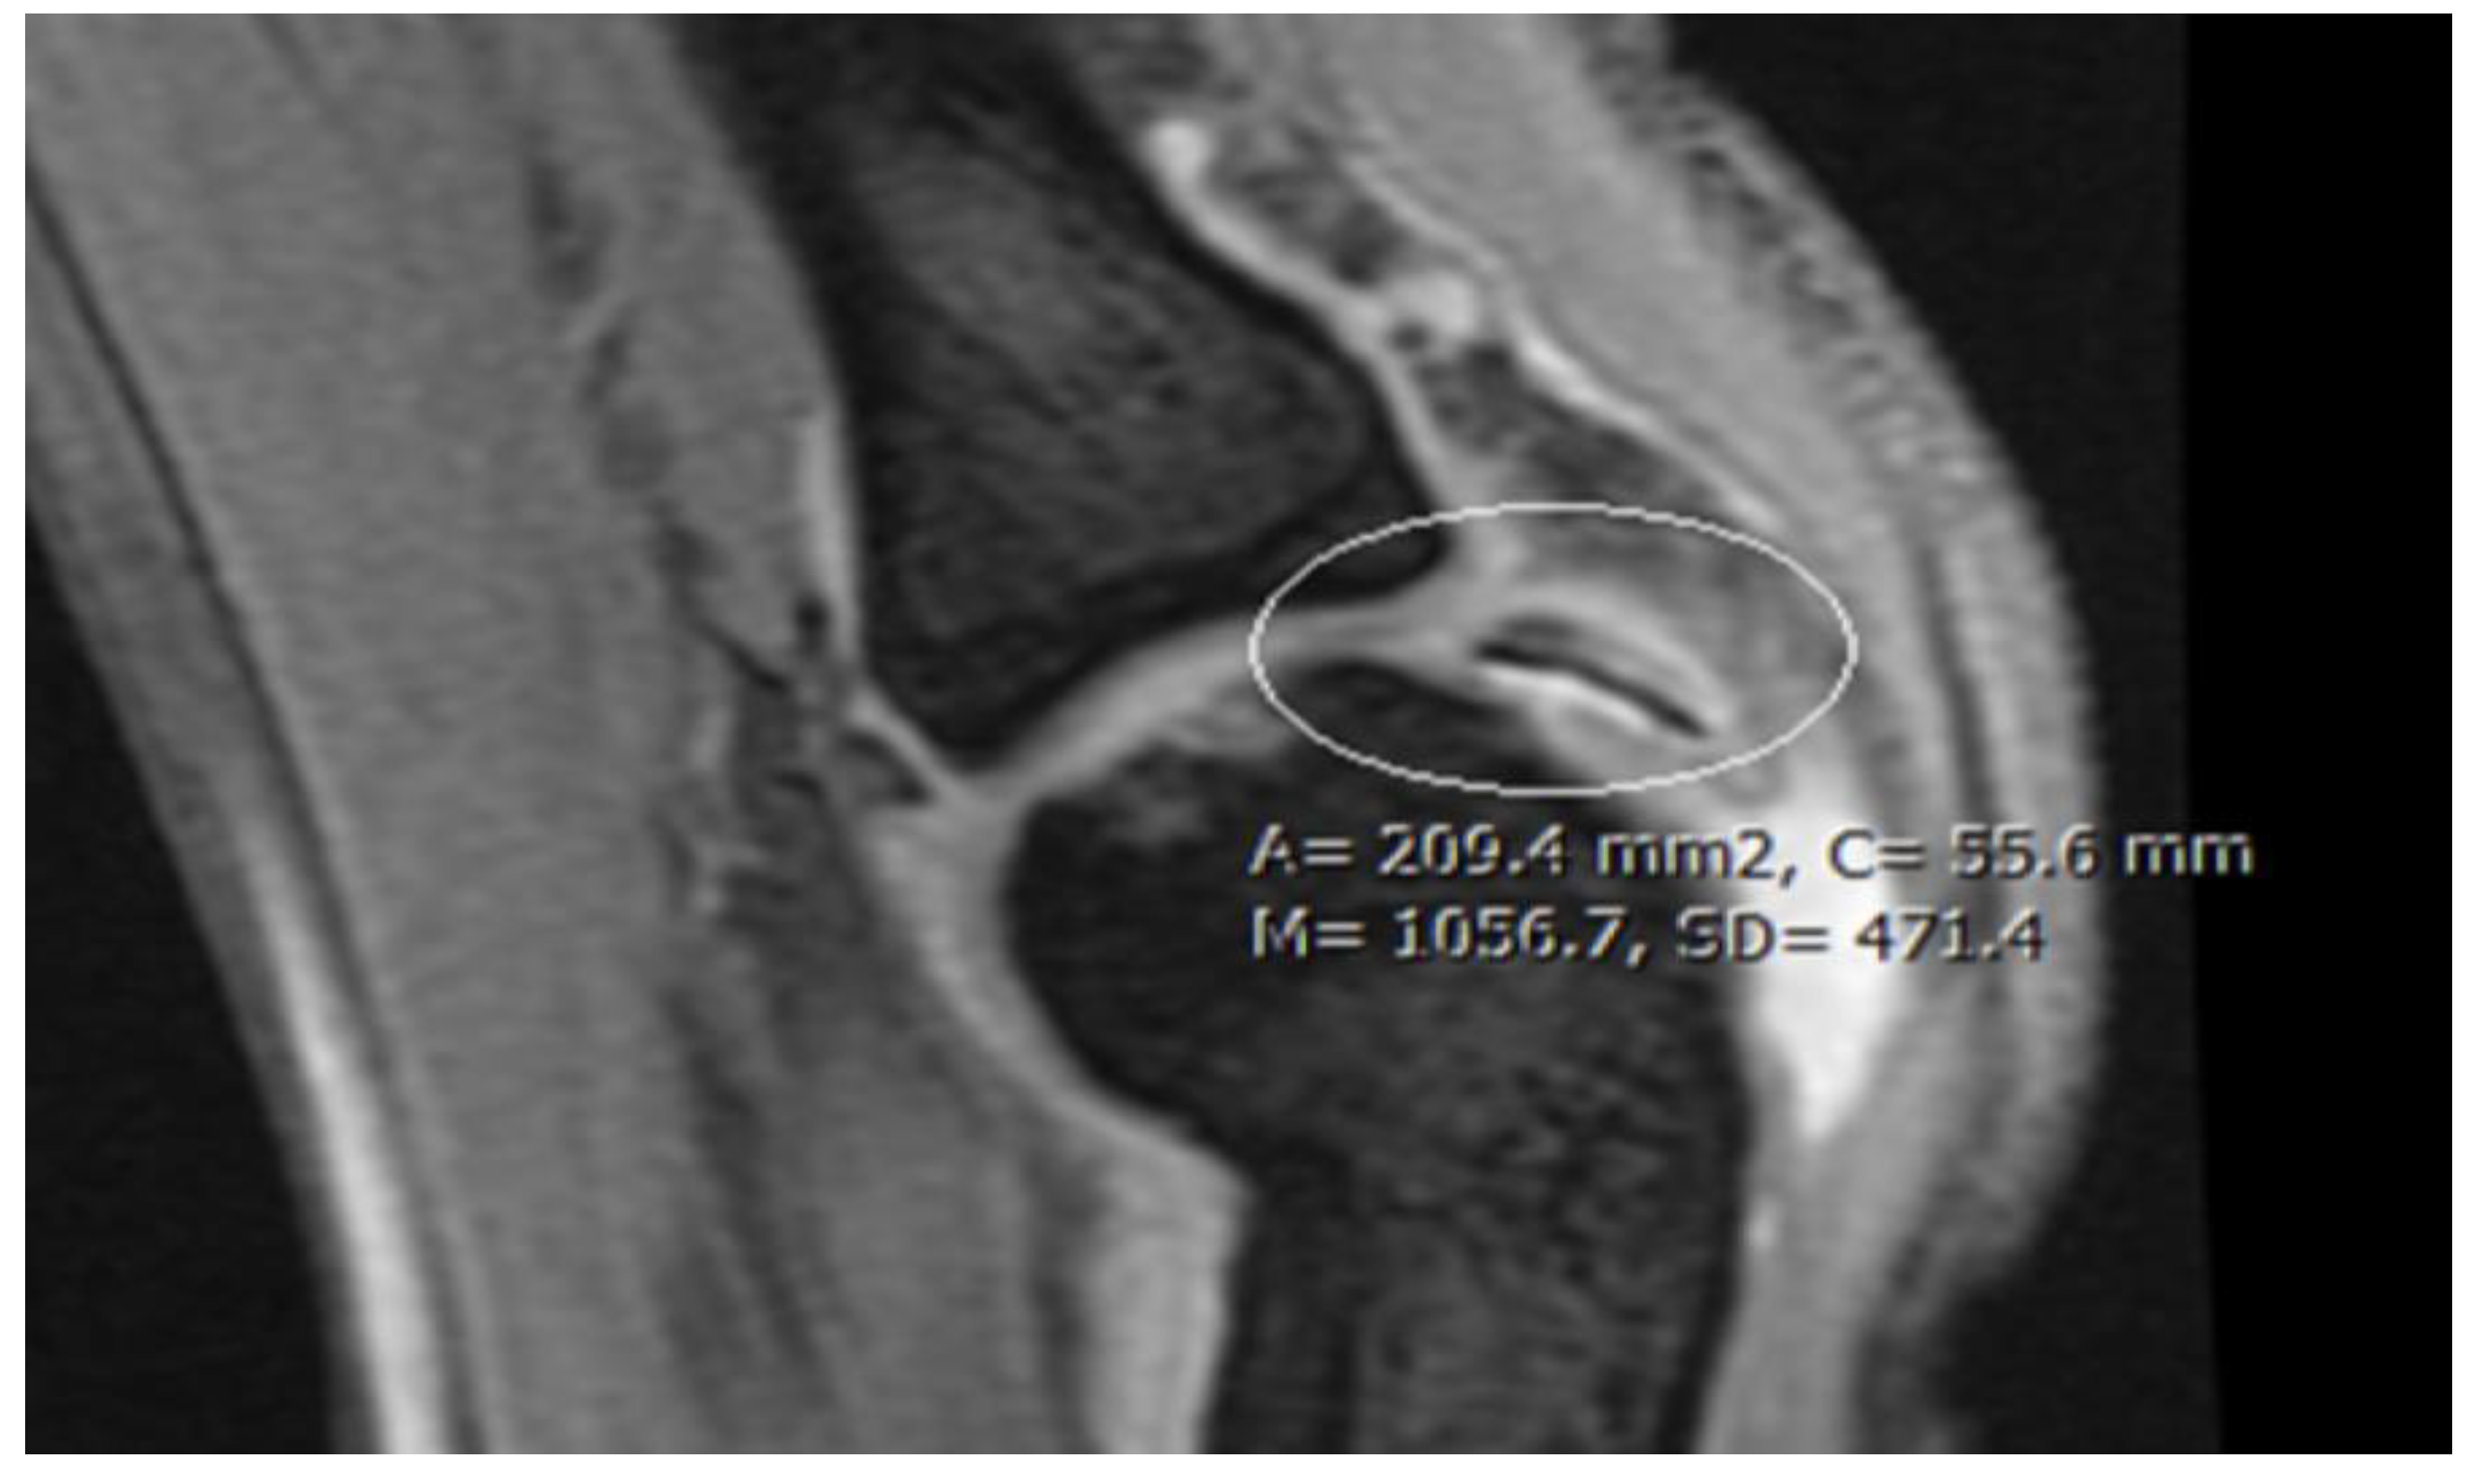

| Stage 1 | Small subchondral compression | Intact Lesion | A stable lesion of the softened area covered by intact cartilage. | Thickening of articular cartilage and low signal changes | Small change of signal, without clear fragment margins. | Epiphyseal cartilage lesion with necrotic center |

| Stage 2 | Partially detached osteochondral fragment | A lesion with signs of early separation | Lesions with partial discontinuity which are stable when probed | Articular cartilage has been breached with a low signal rim behind the fragment indicating fibrous attachment | OSteochondral fragment with clear margins, without fluid in between | Epiphyseal cartilage lesion with complete or incomplete rim calcification |

| Stage 3 | Completely detached, non-displaced | Partially detached lesion | Lesions with complete discontinuity which are not dislocated (Dead in situ) | High signal changes behind the fragment indicate synovial fluid between the fragment and the underlying subchondral bone | Fluid is visible partially between the fragment and bone | Partially or completely ossified lesion |

| Stage 4 | Completely detached and displaced - loose body | Craters with loose bodies (salvageable or non-salvageable) | Empty defect bed with loose or dislocated fragment | Loose body | Fluid surrounds the fragment but it is still in situ | A healed osseous lesion with scar |